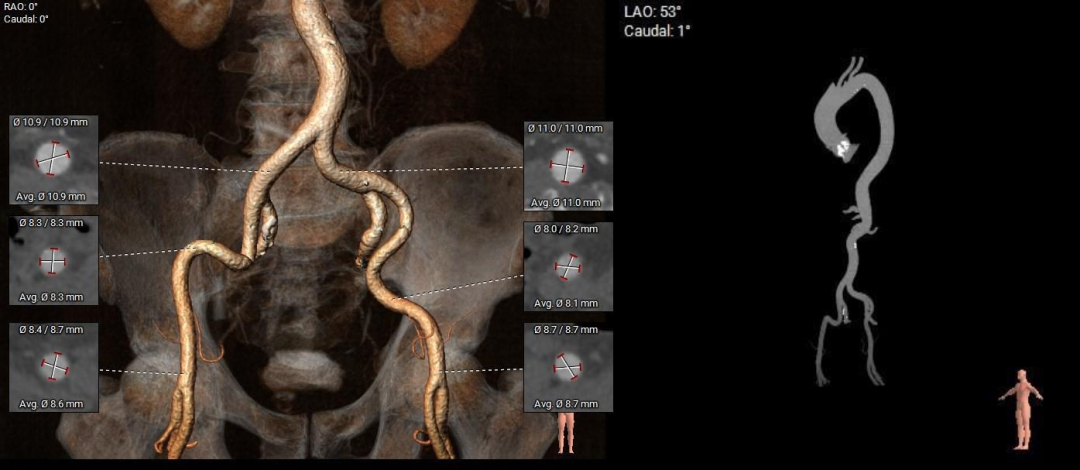

股-髂动脉走行稍迂曲,内径可,右侧股动脉穿刺点偏下位置有钙化块分布,腹主-髂总大量附壁钙化

•股-髂动脉走行稍迂曲,内径可,右侧股动脉穿刺点偏下位置有钙化块分布,腹主-髂总大量附壁钙化,